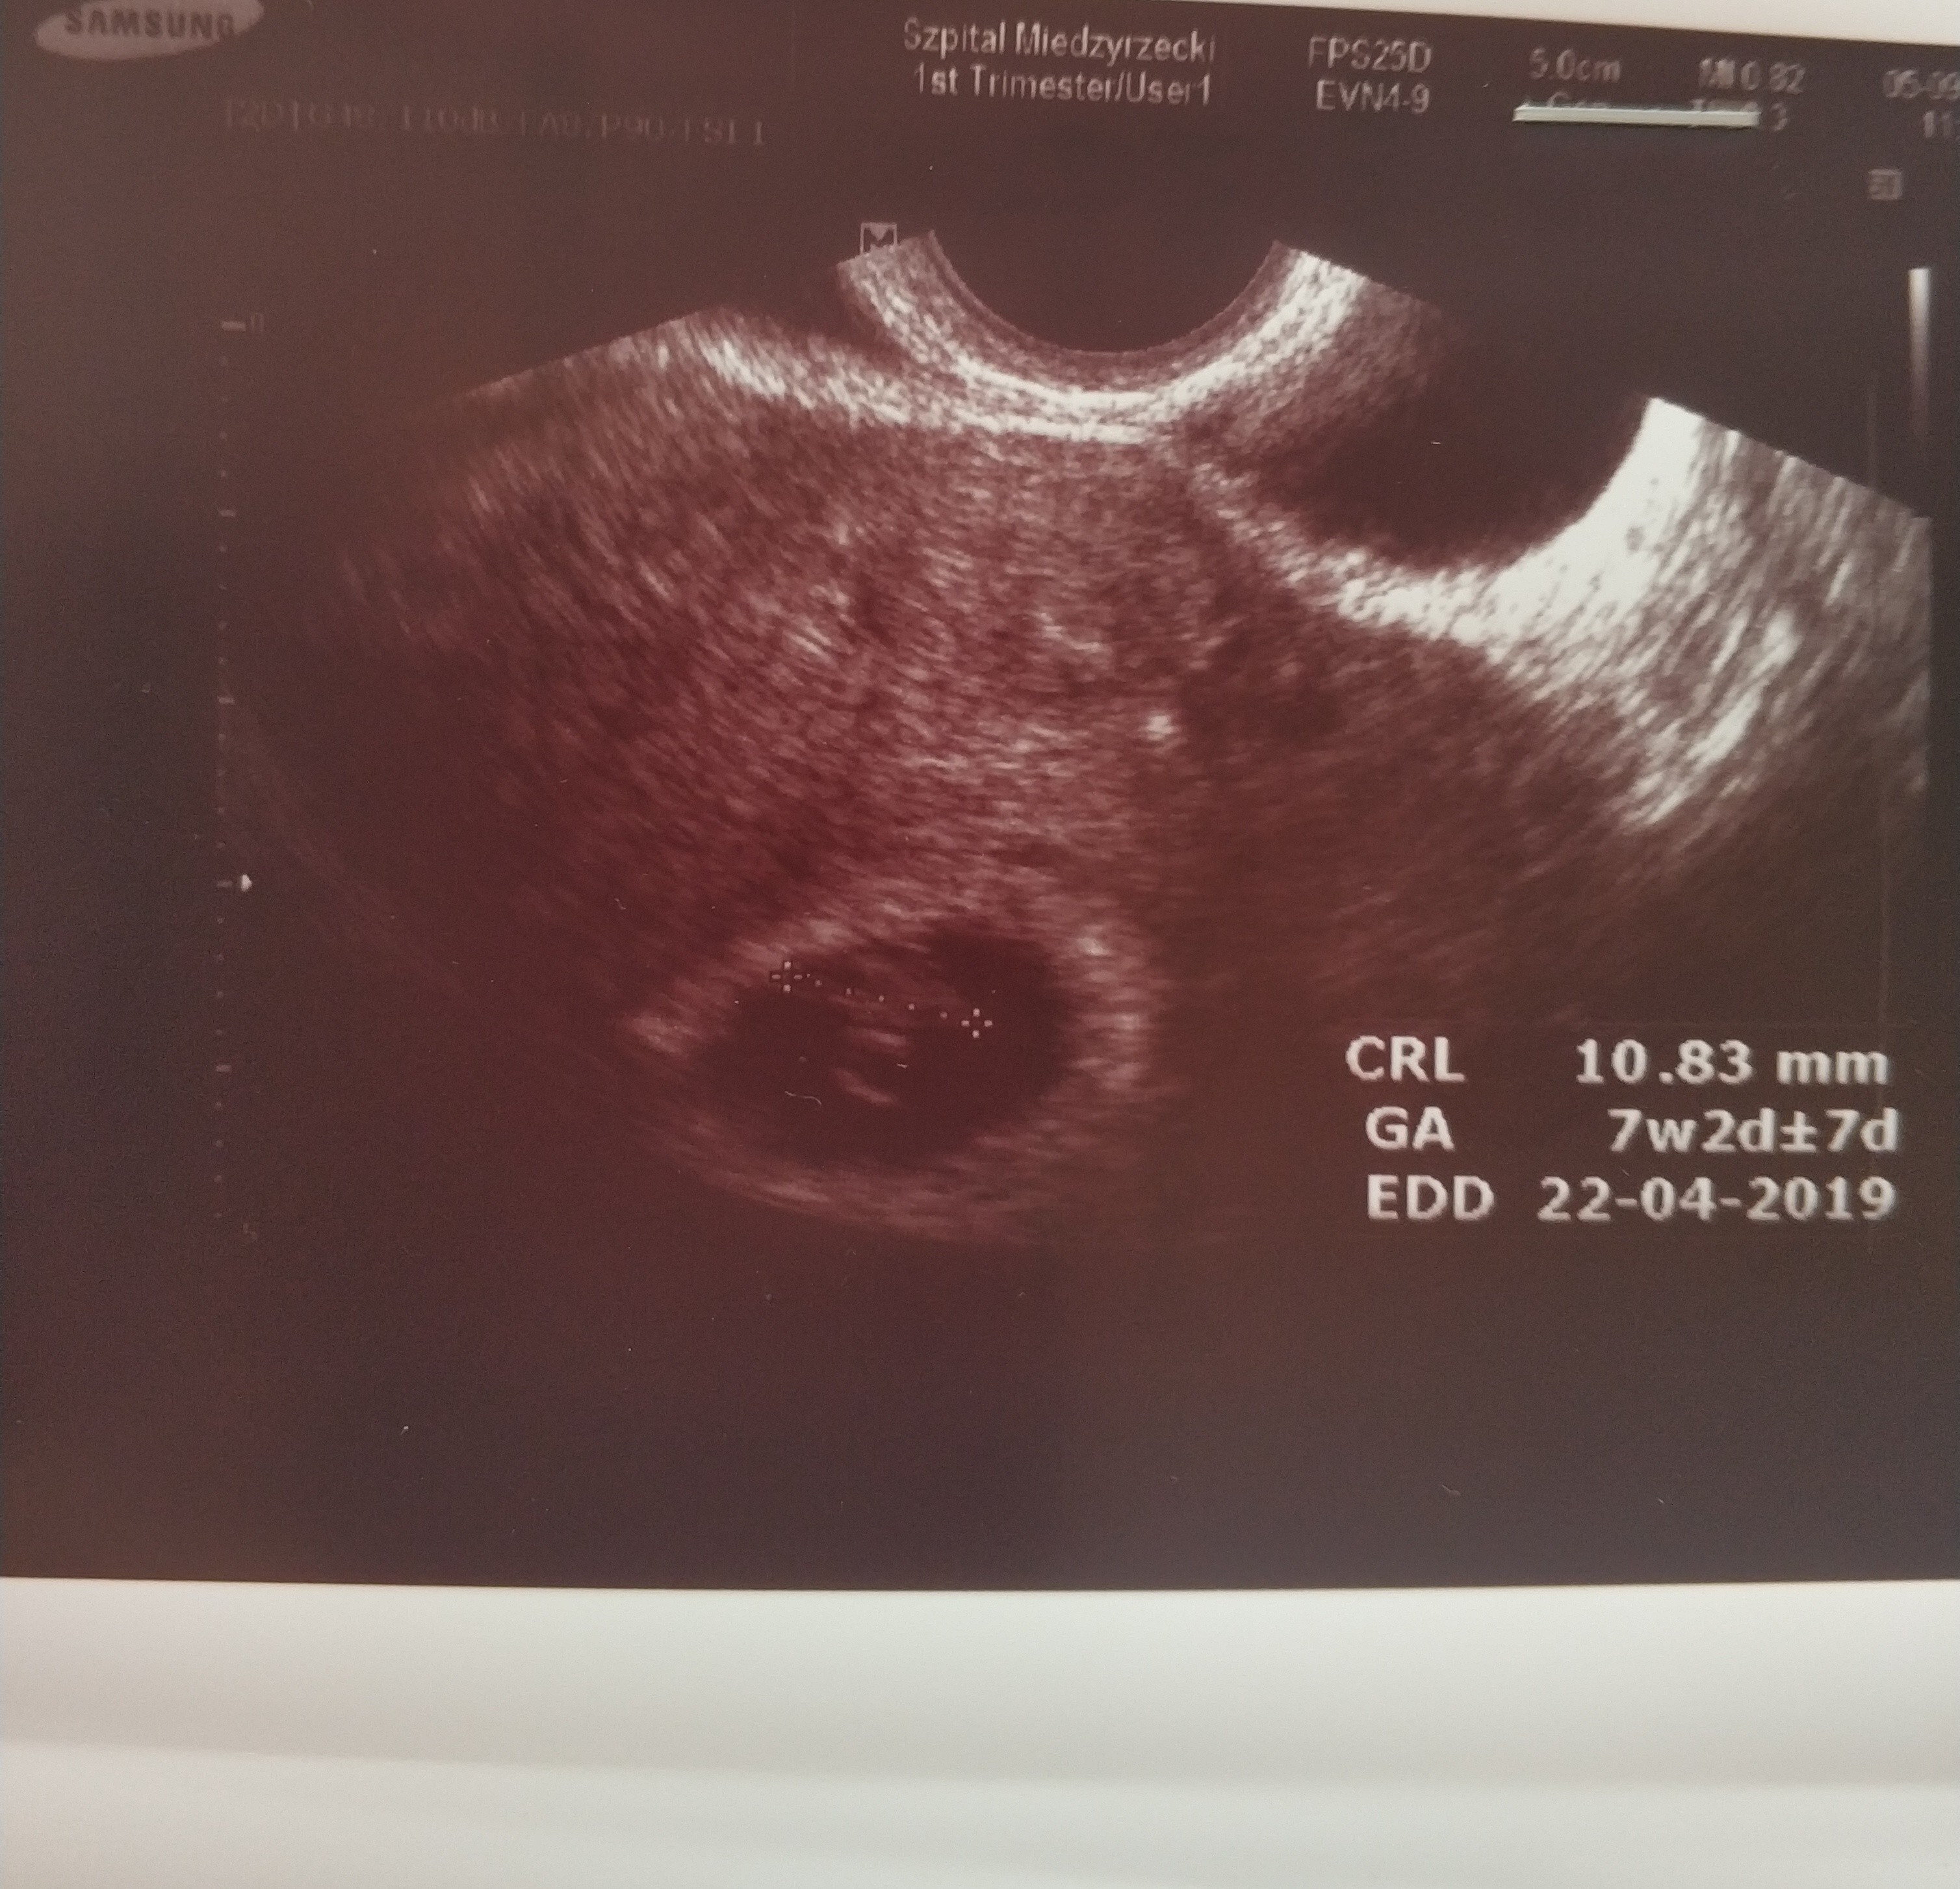

Jest moj mały cudowny kropeczek mierzy 11mm! i widzialam pieknie bijace serduszko. co za widok:)

zycze kazdemu tego doswiadczyc. Ciaza zywa prawidlowa wszystko w jak najlepszym porzadku.

lekarz super.. tak sie balam tej wizyty i jego docinek a tymczasem byl mega profesjonalny i wykazal sie wzgledem mnie wysoką kulturą osobistą. Ale może hajs tak na niego dziala nie wiem... mam watpliwosci na kogo sie zdecydowac.. tego mojego poprzedniego czy tego nowego ktory jest ordynatorem u nas na oddziale. Termin porodu przeskoczyl mi na 22 kwietnia. Wg OM mam 7+3 wg USG 7+2.

zalaczam zdj mojego kropeczka.